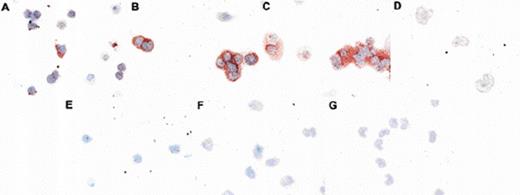

Expression of p21 and p27 in CD34+ blasts and in differentiating cells. (A-F) Cytospins of positively selected CD34+ blasts maintained overnight in low serum after harvest were stained for p21 or p27 as described (Neomarkers MoAbs). Some beads used in the immunoisolation are apparent in the isotype control. Nuclear staining of p27 is evident. Cytospins prepared after 6 days of culture in SCF, G-CSF, and IL-3 were simultaneously stained. Nuclear staining of p21 and cytoplasmic staining of p27 is evident. Cells are counterstained with Hoechst. (G-L) Staining of negatively selected CD34+ cells freshly harvested (G) or after 4 days of culture (H-L). (G) Confocal micrograph of cells doubly stained for CD34 (phycoerythrocin, red) and p27 (Alexa-488). A field containing a CD34− cell is shown, enlarged for detail. (H) Photograph of cells doubly stained for p27 (Cy3, red) and CD71 (fluorescein isothiocyanate [FITC]). After days of culture, 86% of the cells were positive for CD71. (I) Confocal micrograph of cells doubly stained for Ki-67 (Cy3) and p27 (Alexa-48). Nuclear Ki-67 and cytoplasmic p27 is evident. Overlapping nuclear signals are yellow. (J) Isotype control for (I). All isotype controls were similarly negative. (K, L) Confocal microscopy of cells for p27, using C-terminal (G) and N-terminal (L) (Santa Cruz) antibodies.

To first characterize the expression of p21 and p27 in quiescent CD34+ blasts and their differentiating progeny, we immunostained cytospins of CD34+ blasts and of CD34+ cells cultured in cytokines for 6 days. Freshly harvested CD34+ were subjected to immunohistochemical staining for p21 or p27 after overnight culture in low serum to facilitate immunoaffinity bead detachment. Similar results were obtained with immediate staining of cells after chymopapain treatment. As Fig 2 shows, CD34+ blasts were negative for p21 expression when using a sensitive detection system consisting of a biotinylated secondary antibody and streptavidin conjugated Cy3 tertiary staining. Staining with a monoclonal anti-p21 antibody CP36 (courtesy of Brian Dynlacht, MGH, Boston, MA) is shown; similar results were obtained with several commercial antibodies. In contrast to p21, p27 expression is readily evident in nuclei of these cells and can be detected by using either a fluorescent secondary antibody (shown here) or with peroxidase enzymatic detection (see Fig 4). As noted above, the CD34+cells are in G0/G1 phase. The absence of p21 and presence of p27 in the nuclei of these cells suggests that p27, not p21 is contributing to growth arrest of these cells, which is consistent with findings in quiescent lymphocytes.16

Several interesting findings emerge from staining of cells differentiated for 6 days (predominantly myelocytes under our culture conditions). p21 protein is upregulated in the maturing cells, which is consistent with our previous findings14 and is predominantly localized to the nucleus. Surprisingly, the cells develop strong p27 immunoreactivity in the cytoplasm as they differentiate. A reticular staining pattern is evident. The persistent expression of p27 contrasts with downmodulation of p27 protein levels in lymphocytes and in fibroblasts stimulated to enter the cell cycle.4,16 The cytoplasmic localization of p27 is distinct from the predominantly nuclear localization reported for p27 transfected into mink lung epithelial cells.17 In that study, forced cytoplasmic expression of p27 eliminated cdk4 sequestration by cytoplasmic p15. The persistence of p27 expression in proliferating and differentiating myeloid cells was also confirmed by Western blotting and Northern blotting (Fig 3). A single band of the correct size is recognized in differenting cells by the monoclonal used in immunostaining; the identity of an additional, slowly migrating band most prominent in CD34+ blasts is under investigation. This band is repeatable with other antibodies; we note that ubiquitinated p27 gives a prominent band at this position.18 p27 message is constant during differentiation (Fig 3) in contrast to p21 message, which is upregulated as we have previously reported.1 14

The relocalization of p27 in differentiating cells was confirmed by using confocal microscopy as well as by using antibodies recognizing distinct epitopes and by staining different fixation conditions (Figs 2and 4). Confocal microscopy and Western blotting (Fig 3C) was used to verify that cytospin staining showed p27 in the nuclei of CD34+ blasts rather than in overlying cytoplasm. Figure 2G shows a representative confocal image of a CD34+ and CD34− cell present in a population of cells enriched for CD34+ by negative selection. Nuclear p27 (green) is present in the CD34+ cell; nuclear and cytoplasmic p27 is evident in the larger CD34− cell. p27 persistence and localization was also examined in cells stimulated to proliferate by 4 days of culture in G-CSF, SCF, and IL-3 (Fig 2H-2L). In Fig 2H, cells stained both for p27 and for the CD71 (transferrin receptor), a marker of proliferation, are photographed. A smaller blast and a larger cell positive both for CD71 (green) and p27 (red) are shown. Figure 2I shows confocal microscopy of cells doubly stained for the proliferation marker Ki-67 (red) and for p27 (green). Isotype-control–stained cells are shown in Fig 2J. The presence of p27 in Ki-67+ cells is evident. Moreover, whereas Ki-67 only stains the cell nucleus, p27 is also present in the cytoplasm; cytoplasmic p27 appears to be associated with cellular proliferation. Figures 2K and 2L are representative confocal micrographs of differentiating cells after 4 days of culture stained with C-terminal or N-terminal p27 antibodies, respectively. Both nuclear and cytoplasmic staining is evident when using antibodies specific for either epitope. The relocalization of p27 in differentiating cells was confirmed by using peroxidase as an alternative staining and fixation procedure. A third pattern of immunoreactivity was seen as cells moved into the postmitotic compartment, with nuclear p27 staining and perinuclear accentuation in metamyelocytes and bands (Fig 4).